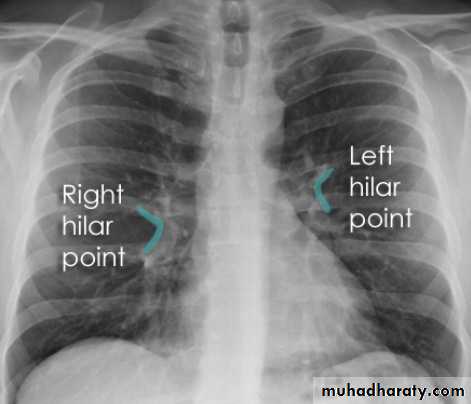

Hilar structuresThe hila (lung roots) are complicated structures mainly consisting of the major bronchi and the pulmonary veins and arteries. These structures pass through the narrow hila on each side and then branch as they widen out into the lungs. The hila are not symmetrical but contain the same basic structures on each side.

The left hilum is often higher than the right

Both hila should be of similar size and density. If either hilum is bigger and more dense, this is a good indication that there is an abnormality.

Lung markings reflects pulmonary vasculature